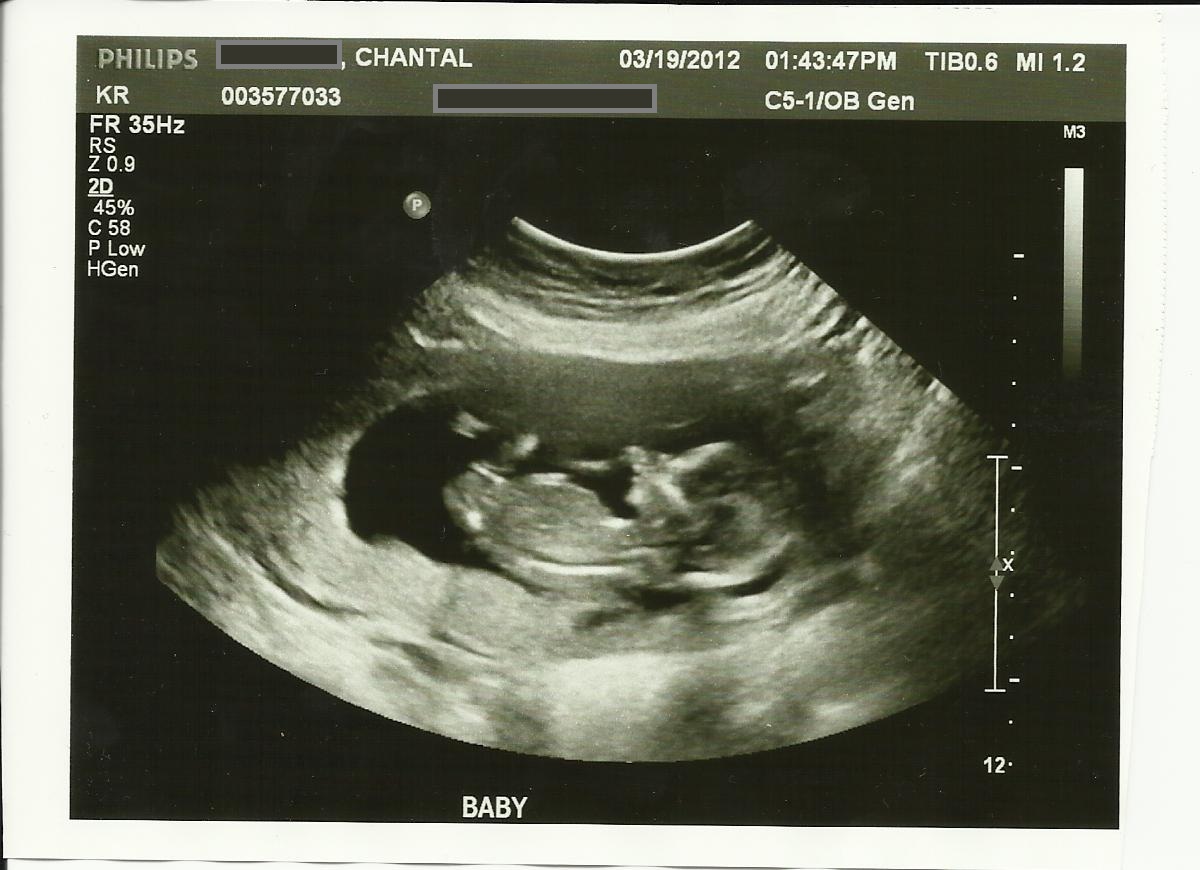

13w5d

Attachment 2240